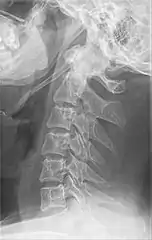

Anteroposterior and lateral radiographs of cervical spine showing ossification of the stylohyoid ligament on both sides

Eagle syndrome occurs due to elongation of the styloid process or calcification of the stylohyoid ligament, potentially compressing the nearby carotid arteryor glossopharyngeal nerve.[4] However, the cause of the elongation hasn’t been known clearly. It could occur spontaneously or could arise since birth. Usually normal stylohyoid process is 2.5–3 cm in length, if the length is longer than 3 cm, it is classified as an elongated stylohyoid process.[10] There are reports of eagles syndrome been elicited after wisdom tooth removal. [11]

Imaging is important and is diagnostic. Visualizing the styloid process on a CT scan with 3D reconstruction is the suggested imaging technique.[12] The enlarged styloid may be visible on an orthopantogram or a lateral soft tissue X ray of the neck.